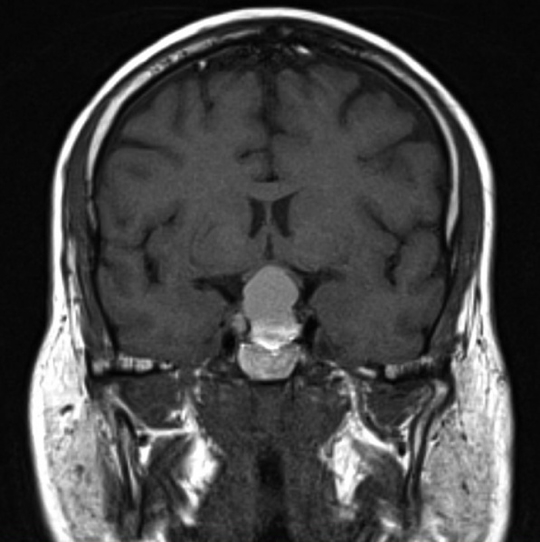

Pituitary Adenoma

- Origin: Anterior pituitary cells

- Features:

- Headache

- Bitemporal hemianopsia (optic chiasm compression)

- Hypopituitarism or hormone hypersecretion

- Treatment: Trans-sphenoidal surgery + hormone therapy

- Prognosis: Good, but recurrence common